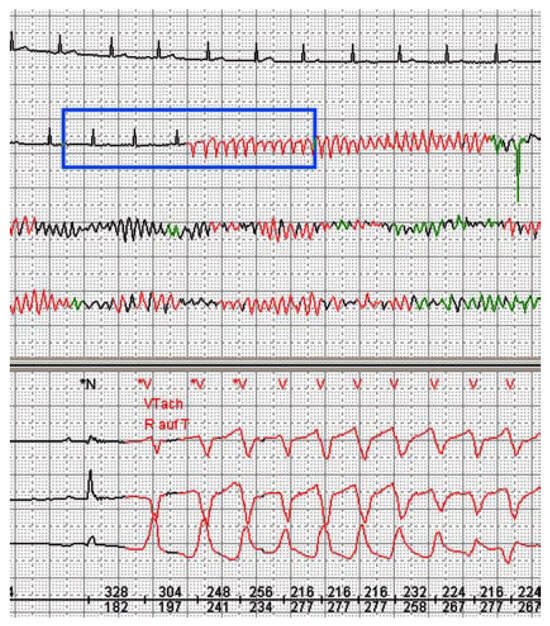

Mechanism of Sudden Cardiac Death in Coronary Artery Disease

Case report